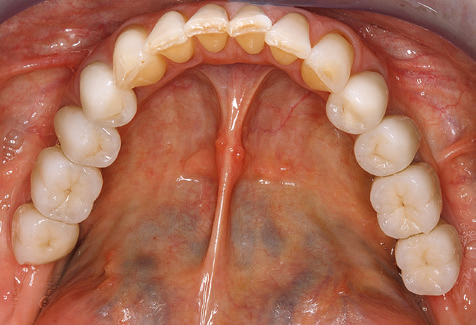

Un'assistenza standardizzata e regolare a misura di rischio nell'ambito di SPT è la chiave per il successo del trattamento clinico a lungo termine nei pazienti con situazione periodontale compromessa. Ciò è particolarmente vero per i pazienti a cui vengono applicati impianti dopo il trattamento parodontale completato con successo (Fig. 11a e b).